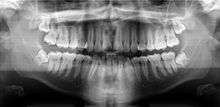

A panoramic radiograph is a panoramic scanning dental X-ray of the upper and lower jaw. It shows a two-dimensional view of a half-circle from ear to ear. Panoramic radiography is a form of tomography; thus, images of multiple planes are taken to make up the composite panoramic image, where the maxilla and mandible are in the focal trough and the structures that are superficial and deep to the trough are blurred.

A dental panoramic radiograph, showing the maxilla and mandible, all the teeth including the "wisdom teeth," the frontal and maxillary sinuses, the nasal cavity and the temporomandibular joint and other near by head and neck anatomy. | |